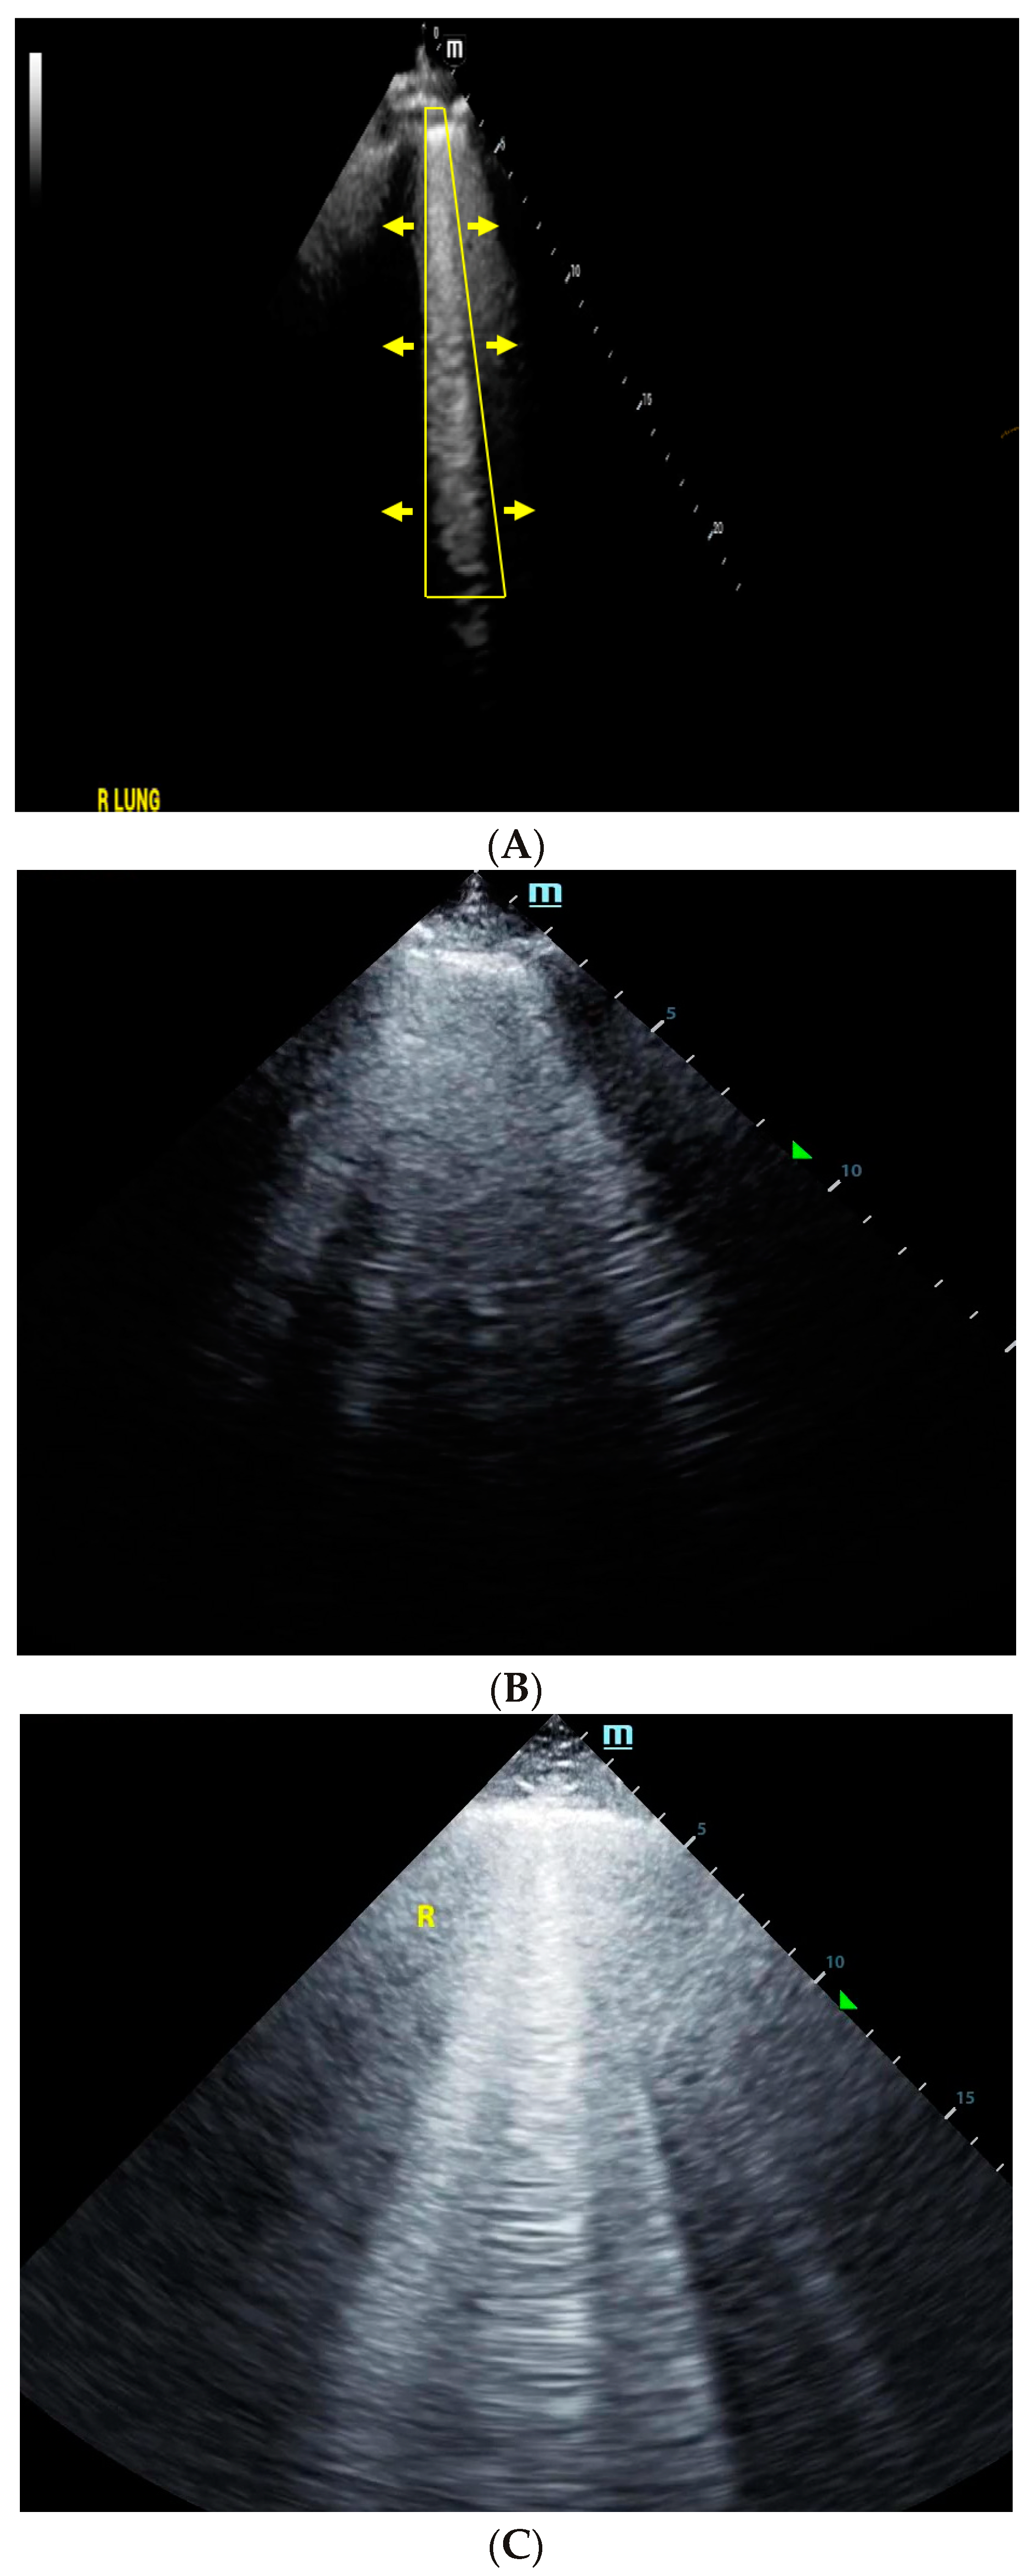

4. Lung Ultrasound